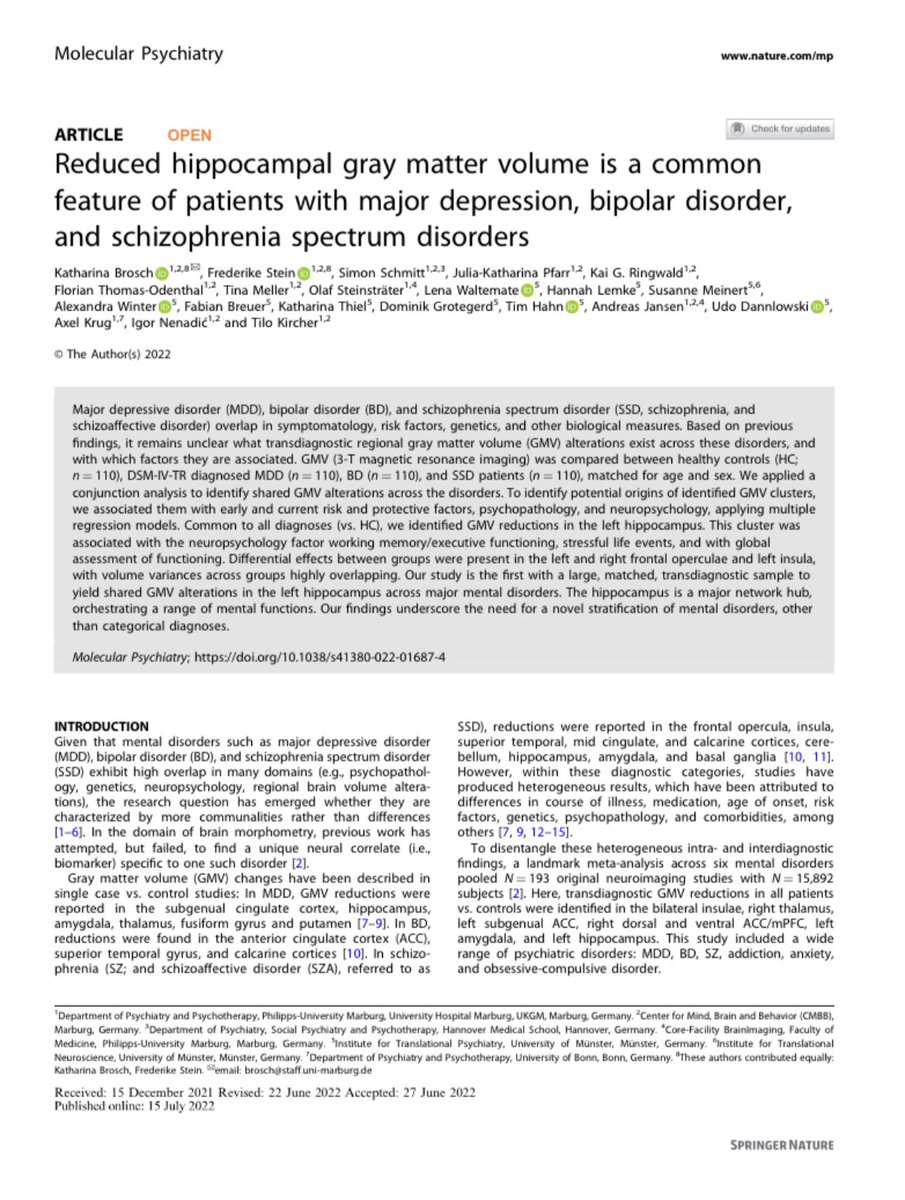

Ahhh this is so cool 🎉🎉🎉 Im so excited for those two Dr. Katharina Brosch Frederike Stein and thrilled to be a part of it #paperthread ⬇️

Super excited to share our molecularpsychiatry paper on shared GMV alterations across MDD, BD, and SSD🥳. Loved working with Dr. Katharina Brosch and all other colleagues of #FOR2107. Results below ⬇️ #ScienceTwitter #neuroscience